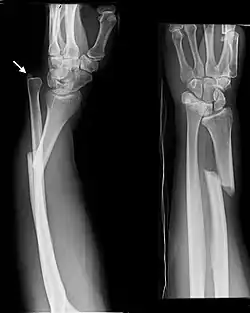

- Galeazzi fracture - not a fracture of the ulna but a displaced fracture of the radius accompanied by a dislocation of the ulna at the wrist, where the radius and ulna come together.[2]

Galeazzi facture (displaced fracture of the radius)